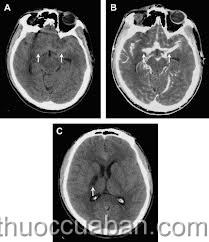

Tràn dịch não

Tràn dịch màng nãoĐại cương

Thông thường, dịch não tủy của trẻ vẫn được tiết ra mỗi ngày, đồng thời các mạch máu não cũng hấp thu hết số dịch này để thải ra. Ở trẻ mắc bệnh, não không thể tự cân bằng được, lượng dịch não tủy tiết ra nhiều hơn so với lượng dịch hấp thu vào máu, làm cho nước bị ứ ở não.